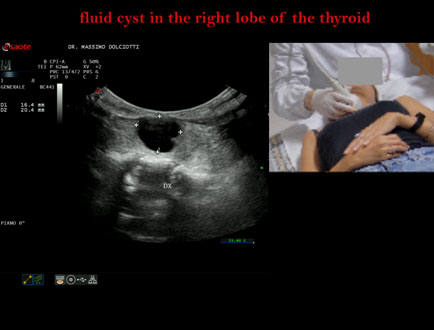

Data inserimento: 05/11/2025

Ecografia del: 27/10/2025

Strumento: Esaote MyLab Eight

Sonda: Lineare Multifrequenza 3-13 MHz e Volumetrica Multifrequenza 1-8 MHz

Età Paziente: F 44 anni

Motivazione dell'esame: rapida comparsa di tumefazione in sede cervicale anteriore, lievemente dolente alla palpazione.

Commento all'esame: le immagini ed il video documentano al terzo medio del lobo destro della tiroide, formazione anecogena, a margini regolari, senza segni di vascolarizzazione, delle dimensioni di 16,9 x 19 mm, da ricondurre a cisti liquida.

Conclusioni: cisti liquida al lobo destro della tiroide (fluid cyst in the right lobe of the thyroid).

Presentazione: Dr. Massimo Dolciotti - Ancona

Elaborazione digitale: Andrea Dini - Ancona